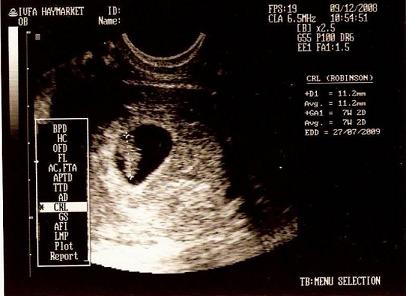

孕囊大小看男女之看孕囊b超图

首先数据不能超过8周的,40多天是最合适的。然后就是要有3个数据的,没有3个数据的,一律不能判断,孕囊都是圆柱状的,每个B超师做B超的时候,截面会截取的方位不一样,有的横截面,有的截取竖截面,所以,看图片是长的还是圆的,不能判断男女。

打个比方,比如40*20mm的孕囊,这样根本没有办法判断,表面上看两个数据相差一倍,应该是男孩,错了,因为没有第三个数据,如果是40*40*20,那肯定是男孩,但是如果B超师横截面时,孕囊就成了40*40mm的两个数据,看上去就是圆的了,然后造成了,孕囊是圆的,结果怎么生出了儿子,貌似不准的误导。所以数据一定要有3个。

如果孕囊成等差数列,比如40*30*20,这样就是女孩,但是如果B超师取了40*20的截面,貌似男孩的数据,结果生出了闺女,造成孕囊看男女不准的说法。

记住:2个数据的话,看不了,因为每个B超师获取孕囊的方位不一样,所以不能判断,有3个数据的,是最好判断的,两个数据差不多,第三个数据比前两个小一倍,那肯定是儿子,如果成递减数据就是女儿。